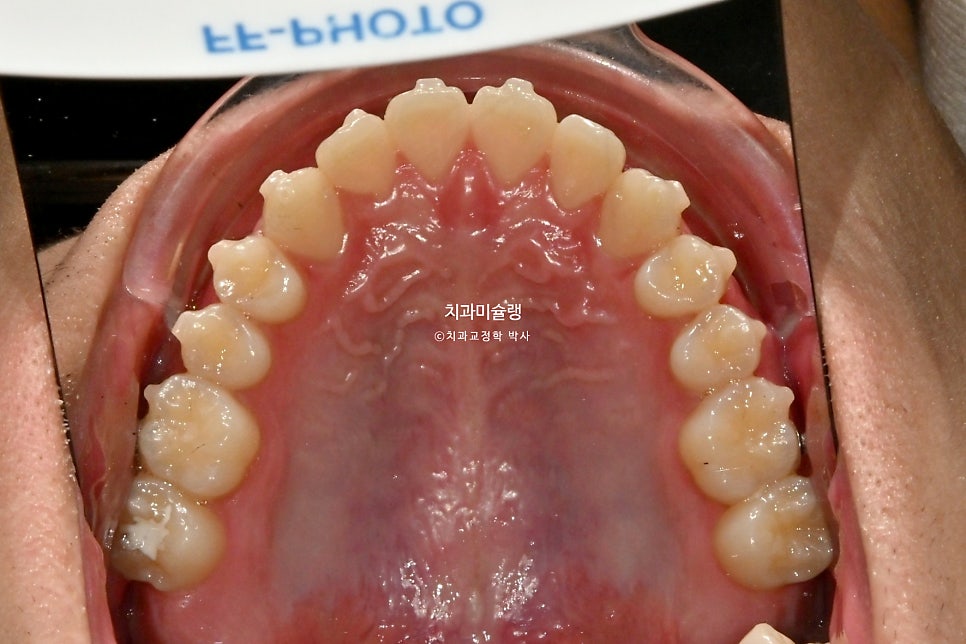

2026년 3월 – 치료 완료

중심선은 정확히 맞으며

어금니 교합관계는 좌우 모두 1급을 달성

치료 전후 비교 결과

이제 전후 비교 보겠습니다.

간단한 교정이 아니고서야 미진한 부분 전혀 없이, 즉 재제작 없이 치료를 마무리하기 힘든데 해외에서 가끔 내원하면서도 장치를 열심히 껴준 덕에

쉽지 않는 난이도의 치료를 재제작 없이 마무리 했습니다.

교합관계는 3급에서 1급으로 개선되었죠.